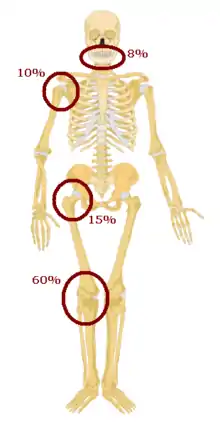

Osteosarcomas tend to occur at the sites of bone growth, presumably because proliferation makes osteoblastic cells in this region prone to acquire mutations that could lead to transformation of cells (the RB gene and p53 gene are commonly involved). Due to this tendency, high incidence of osteosarcoma is seen in some large dog breeds (St. Bernards and Great Danes). The tumor may be localized at the end of the long bone (commonly in the metaphysis). Most often it affects the proximal end of tibia or humerus, or distal end of femur. Osteosarcoma tends to affect regions around the knee in 60% of cases, 15% around the hip, 10% at the shoulder, and 8% in the jaw. The tumor is solid, hard, irregular ("fir-tree," "moth-eaten", or "sun-burst" appearance on X-ray examination) due to the tumor spicules of calcified bone radiating in right angles. These right angles form what is known as a Codman triangle, which is characteristic but not diagnostic of osteosarcoma. Surrounding tissues are infiltrated.